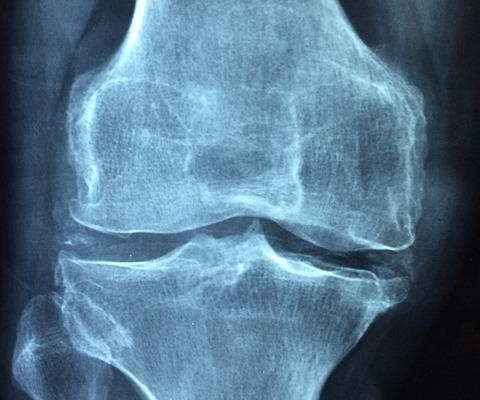

ArthurCare MSK CareLists

Quick reads packed with actionable advice for better musculoskeletal health